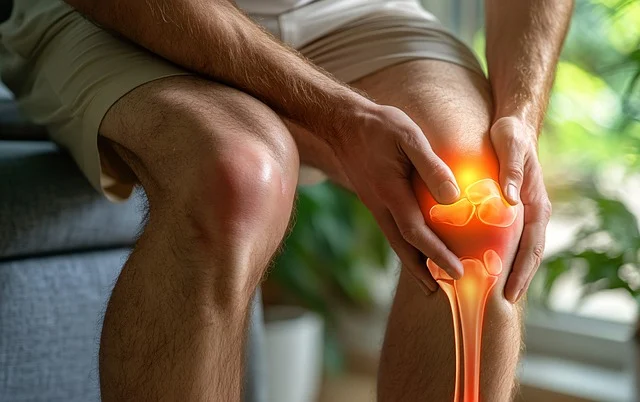

퇴행성 관절염은 일반적으로 나이가 들면서 발생합니다. 이 형태의 관절염은 관절의 연골이 마모되면서 점차 악화되는 현상인데요, 이는 오랜 시간 동안의 반복적인 스트레스나 과사용으로 인해 발생할 수 있습니다. 퇴행성 관절염은 무릎, 엉덩이, 손가락에 주로 발생하며, 증상으로는 통증, 뻣뻣함, 움직일 때 소리가 나는 등의 특징이 있습니다.

퇴행성 관절염의 초기 단계에서 나타나는 증상은 매우 미미하게 시작됩니다. 예를 들어, 아침에 일어났을 때 관절이 뻣뻣한 느낌이 들 수 있습니다. 이는 걷거나 움직일 때 점차 풀리기도 하지만, 단순한 피로나 스트레스로 여겨질 수 있어 종종 간과됩니다. 그러나 이런 초기 증상을 무시하지 말고 적극적으로 관리할 필요가 있습니다.